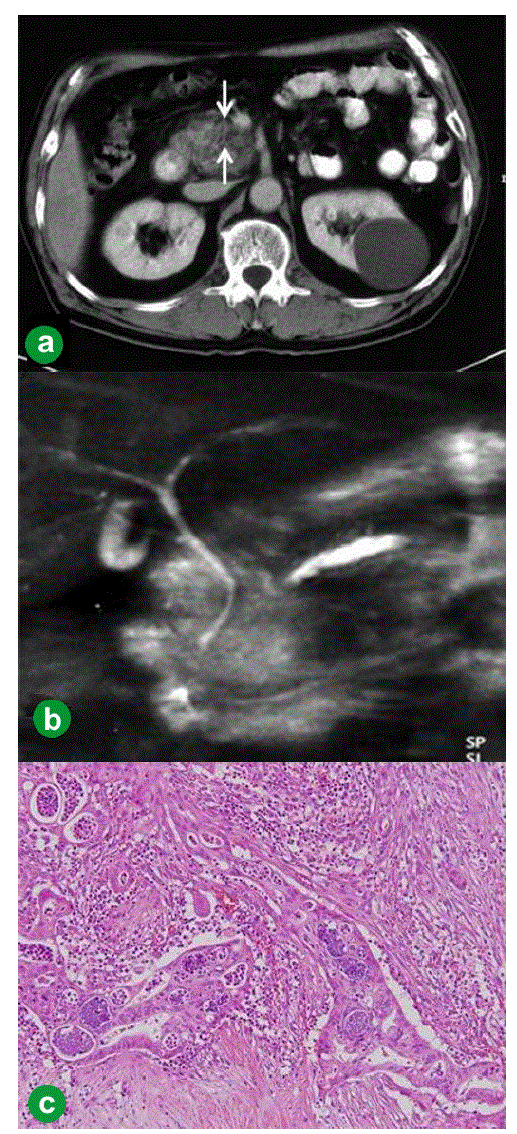

| Figure 1. Case#1: initial operation. a. A tumor approximately 1 cm in diameter was detected in the pancreatic head on abdominal CT (arrow). b. The main pancreatic duct was disrupted, and the main pancreatic duct of the distal pancreas was dilated on MRCP. c. Welldifferentiated tubular carcinoma. Marked fibrosis and acinus atrophy were observed. Mild atypical cells with a slightly swollen nucleus formed an irregular ductal structure and invaded the parenchyma. (H&E stain, x100). |